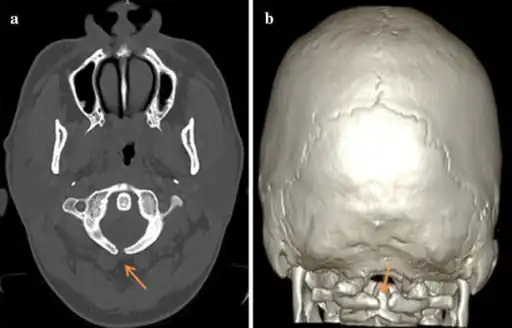

a,b) Atlas spina-bifida oculta

A meningocele may also form through dehiscences in the base of the skull. These may be classified by their localisation to occipital, frontoethmoidal, or nasal. Endonasal meningoceles lie at the roof of the nasal cavity and may be mistaken for a nasal polyp. They are treated surgically. Encephalomeningoceles are classified in the same way and also contain brain tissue.